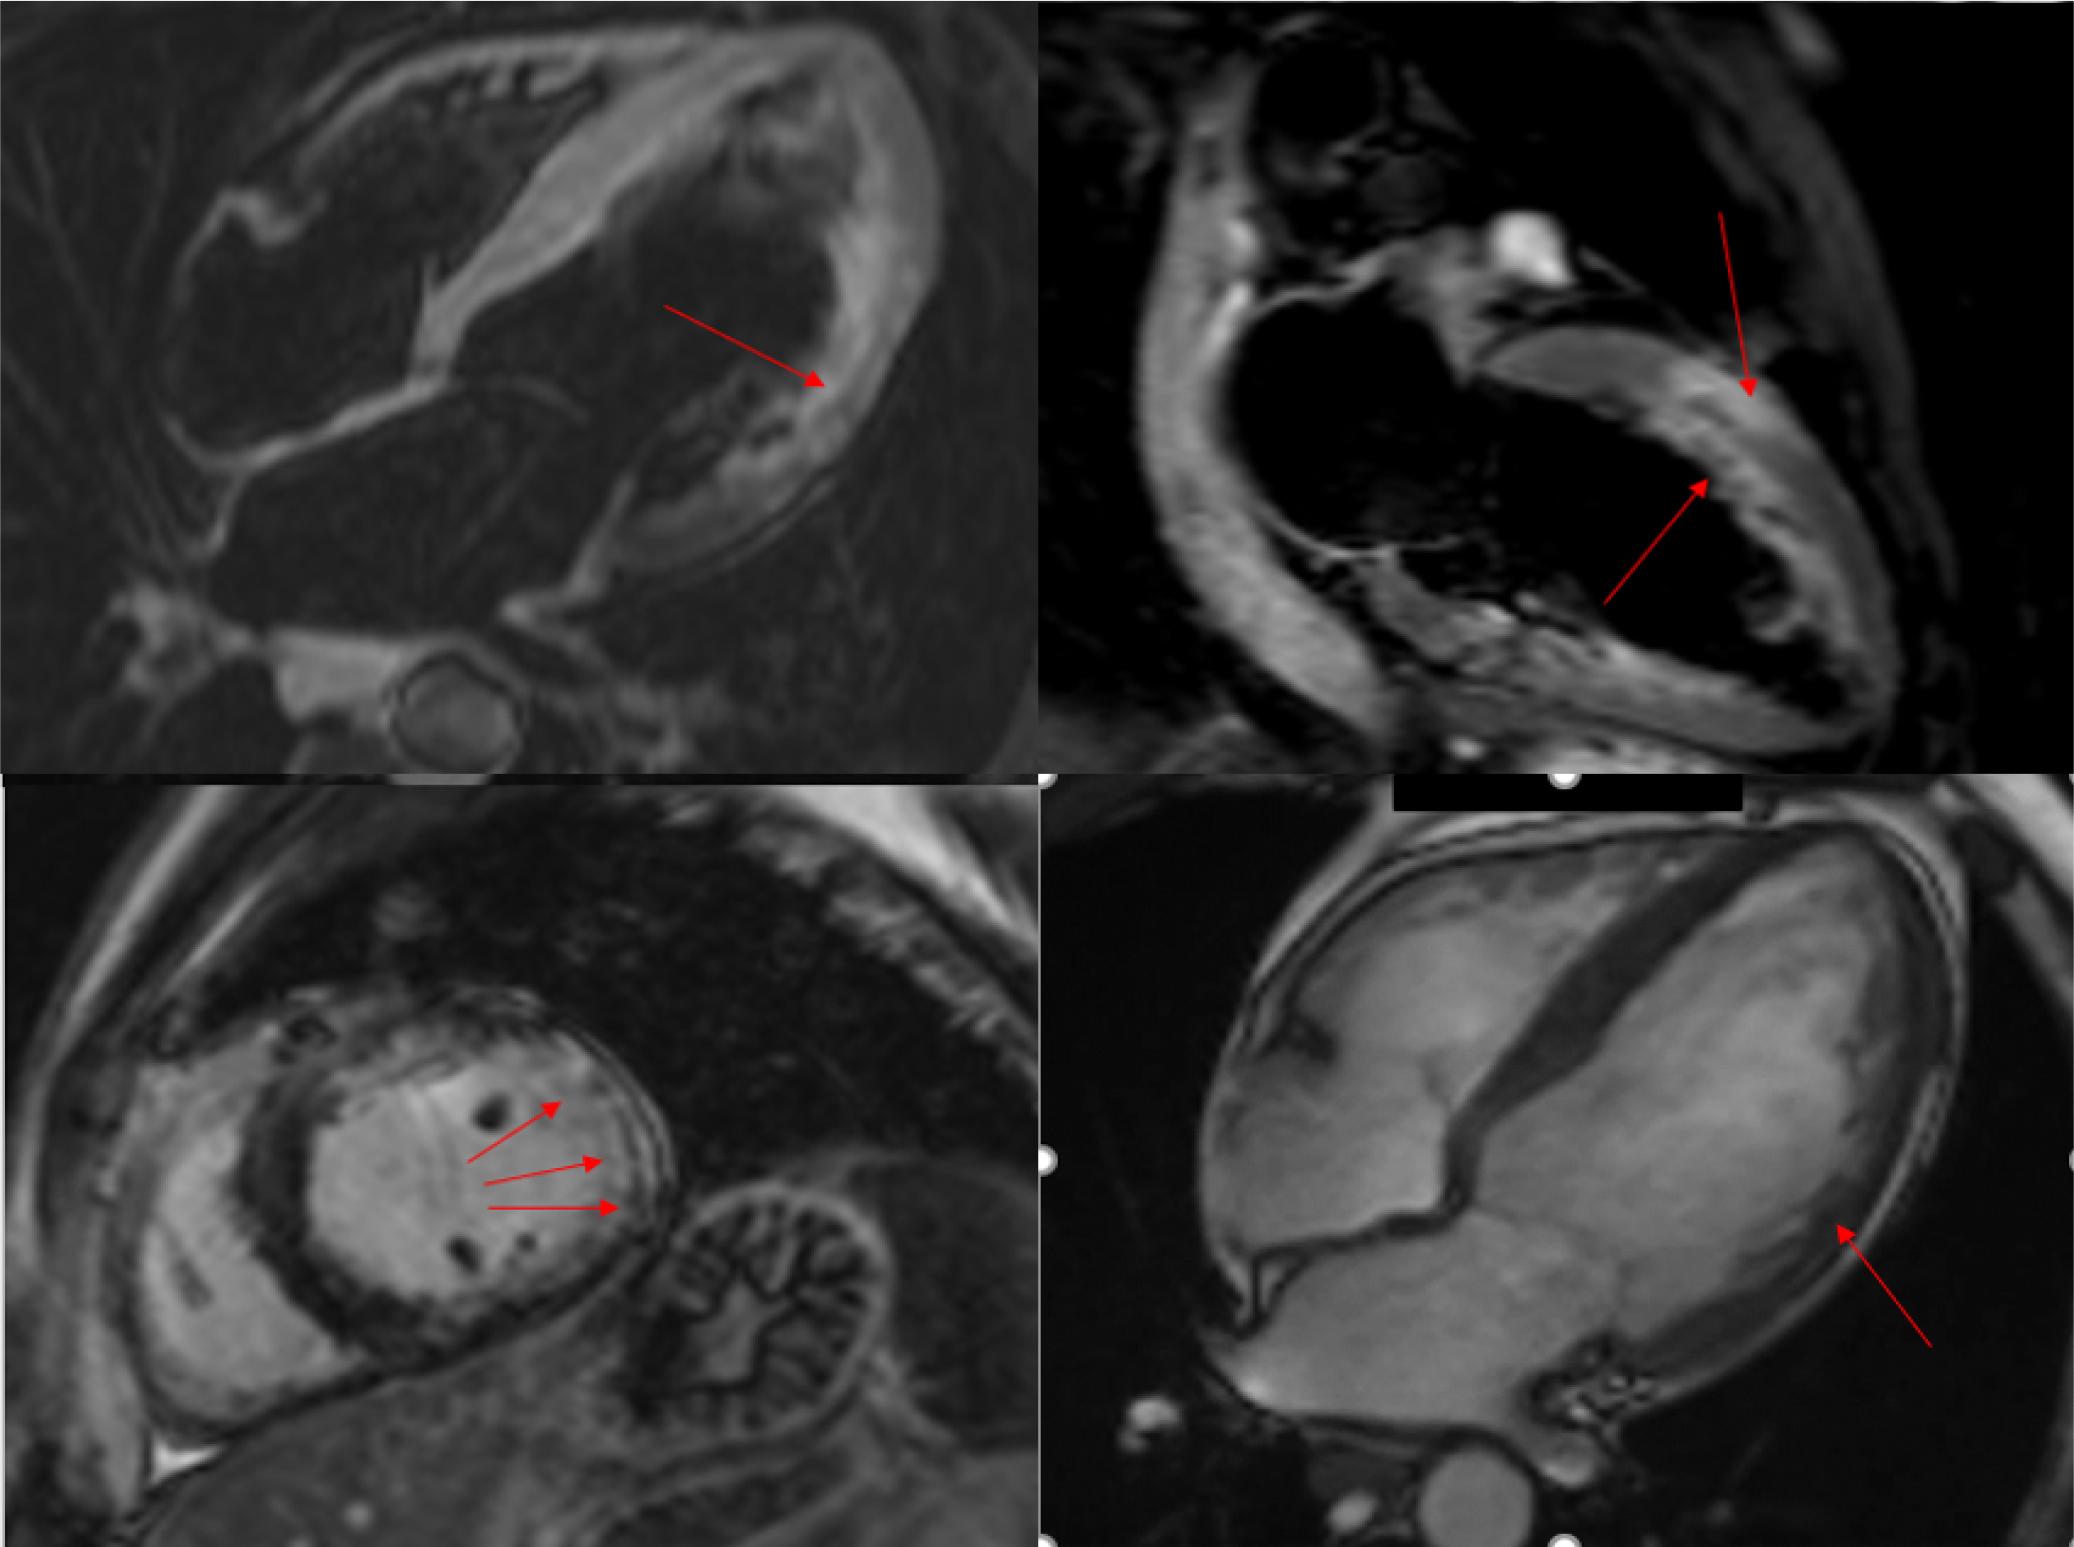

Cardiac MRI showed mild left ventricular dilation, with an EF of 43%. Wall motion abnormalities were observed in the lateral wall (throughout its entire aspect) and the anterior wall (mainly in the middle segment). There was also myocardial late gadolinium enhancement (LGE) with a distribution pattern highly suggestive of scattered and focal infarction without transmural involvement. (Fig. 3)

Cardiac MRI – Mild LV dilation; LVEF – 43 %; Multiple areas of LGE along the middle third of antero-lateral and lateral wall